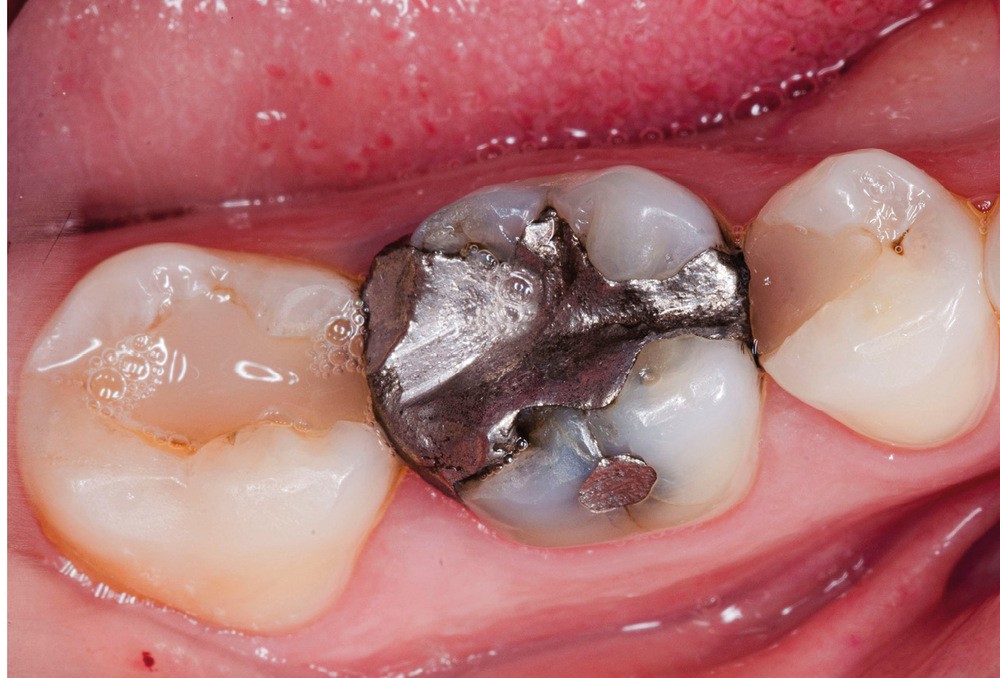

A l’examen clinique, nous observons une restauration à l’amalgame sur 46 non étanche ainsi que des restaurations composites sur 45 et 47 dont les morphologies sont usées (fig. 1). Après réalisation des tests cliniques, nous confirmons que la 46 est à l’origine de la sensibilité décrite par la patiente.